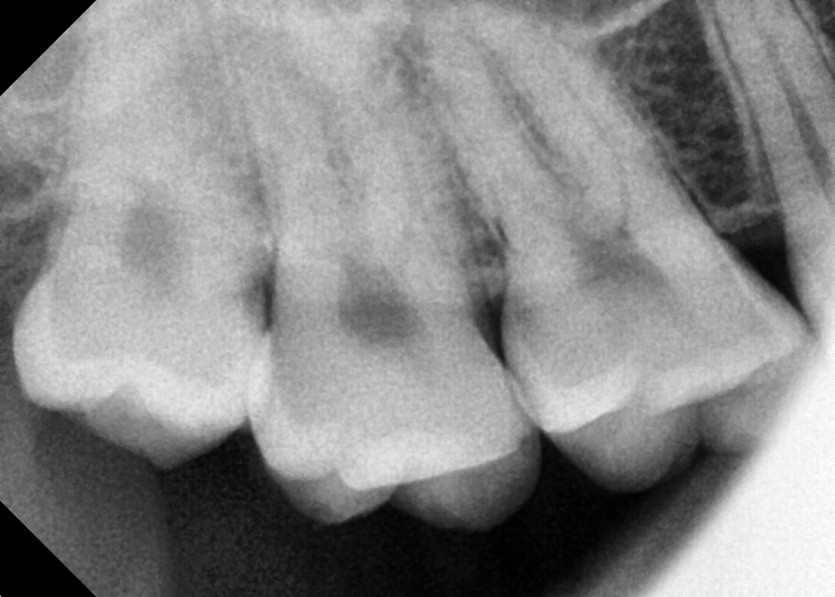

#18,48 사랑니 발치

구강 외과 전문의가 당일 발치했습니다.